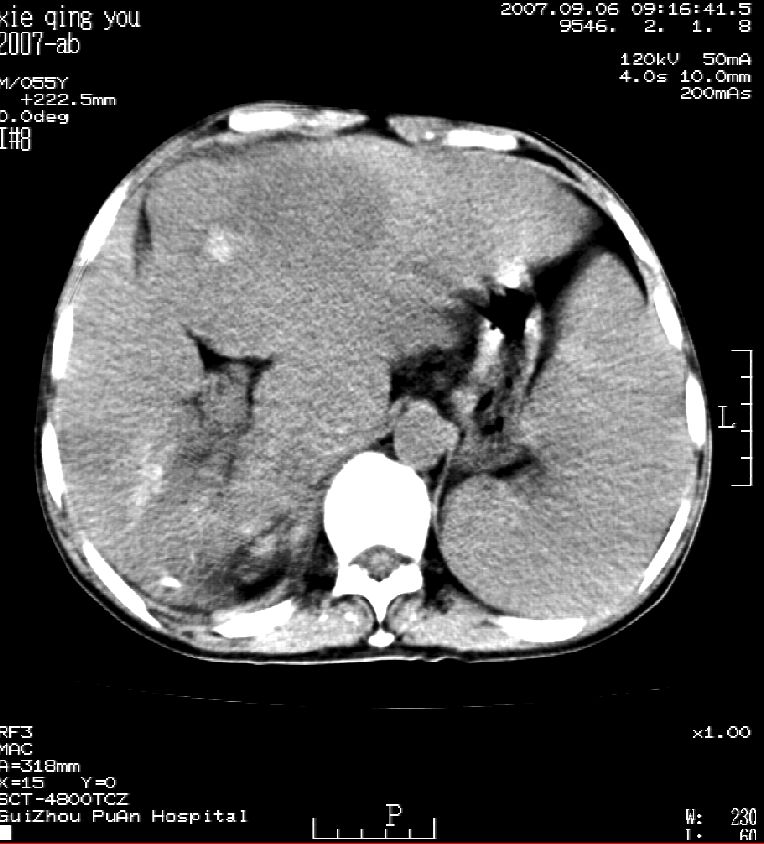

2007年8月片

2007年9月片

这个病灶很有意思,怎么可能没有了呢?我考虑当时很可能是肝脏脓肿(b超示囊肿是有可能误诊的,因为影像表现都是低回声吗?),现在脓肿吸收了,肝脏萎缩,肝裂增宽了.别的肝叶代偿增大,不过现在左内叶的确有个占位,肝内多发结石,脾脏比以前大,不排除有肝硬化可能.建议增强扫描给于定性!!!!

肝硬化\\脾大,肝左叶肝癌可能性大,建议增强扫描.肝内胆管多发性结石.

1, 肝硬化,脾大;2,肝左叶肝癌可能性大,建议增强扫描.3,肝内胆管多发性结石.

考虑肝内胆管多发结石引起的肝内局部炎症,这样可以解释2005年肝右叶病灶的吸收和左叶新病灶.

肝硬化、脾大、肝内胆管多发结石。肝左叶低密度占位。建议增强扫描.排除肝癌